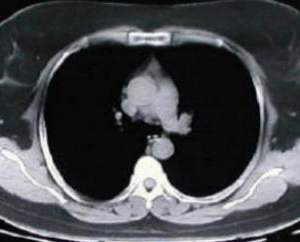

• Estudios de tomografía del tórax, electromiografía, expirometría y prueba terapeutica con edrofonio, son realizados, concluyendo el diagnóstico de miastenia gravis con Timoma, (16 meses despues de iniciados los síntomas).

Tomografía torácica